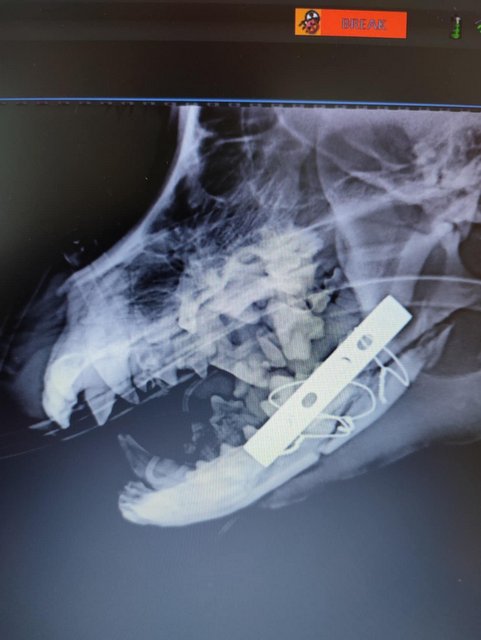

Camush Kopf ist wieder symmetrisch, der Kiefer wird jetzt mit Platte und Verdrahtung zusammengehalten und ein paar Zähne fehlen jetzt.

Ob sein Bein auch noch verplattet wurde, wissen wir noch nicht.

Camush bekommt jetzt 14 Tage Nahrung durch eine Sonde, in der Hoffnung, dass er danach selbsständig futtern kann.

Sein Beinbruch ist ein offener Unterarmbruch von Elle und Speiche, der noch nach Erstversorgung operiert werden muss.